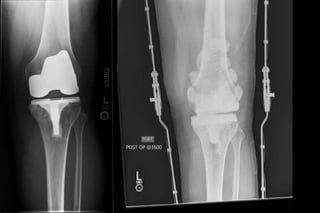

• Knee

–Infection 25%

–Implant loosening/breakage 20%

Overview of Total Joint

Replacement

• Still have not solved long term failures and need

for revisions

–Prosthetic joint infection

–Revisions are complicated

–Revisions have poorer outcomes